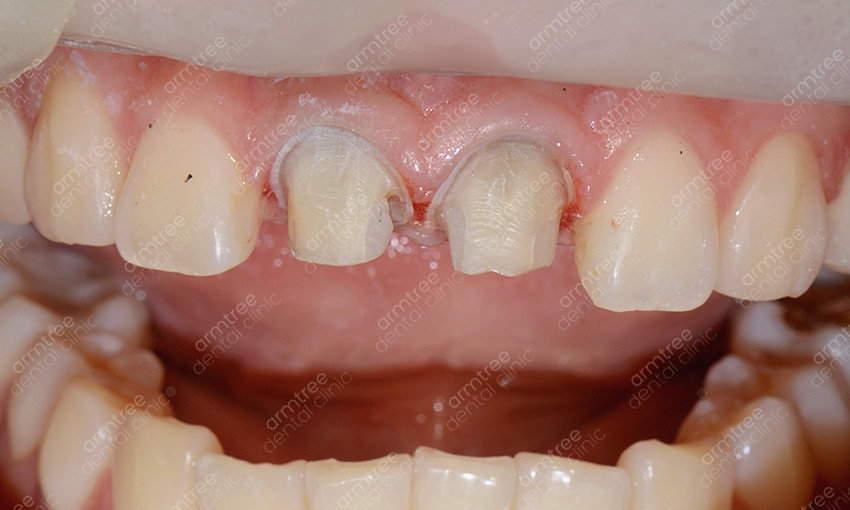

실활치란 용어는 외상이나 충치 등으로 인하여 치아 속 치수가 죽는 증상을 의미해요. 그로 인해 혈액과 신경 활동이 원활하게 이루어지지 않아 치아가 약해지고 어둡게 변하기도 하는 것이에요. 이러한 치아 내부의 출혈 색소나 염증 부산물을 제거하는 신경치료를 선 진행한 후 치아 내부에 미백제를 넣어 다시 치아색을 밝게 한 후 레진으로 막는 치료법이에요. 일반적인 생활치미백에 비해 진행과정이 까다로운 편이기 때문에 관련하여 장비를 갖추고 있고 해당 경험이 풍부한 곳에서 치료를 받는 것이 좋았어요. 신논현역치과 아름드리치과에 사용되는 약재에 대해 신체에 해로울까 걱정하시는 분들도 계시는데요. 사용되는 약재는 치아 속에 과산화수소수 계열의 약재를 넣어놓고 환자가 생활하시는 동안에 미백이 진행되게 하는 것이라 영어로는 Walking blwaching라고도 불리는데요. 실제로 진행 시 치아 하부 구조 사이에 수복재료를 쌓고 진행하는 것이라 전문 의료진과 함께 한다면 크게 위험하지 않은 시술이라고 할 수 있었어요. 하지만 이 역시 정확하게 수복재료를 적용하지 않고 무분별한 진행을 한다면 치아 외 흡수가 발생할 수 있으므로 받드시 경험이 많은 의료진의 시술이 필요한 과정이었어요.

앞니변색으로 미백을 고려하시지만 모든 경우에 해당하여 진행할 수 있는 시술은 아니에요. 치아가가 활력을 잃어 변색이 된 경우에는 실활치 미백으로 치료하는 것이 보통의 경우이지만 정도가 심각한 경우에는 미백 시술만으로 호전되지 않기 때문에 라미네이트나 올세라믹 같은 심미보철치료가 필요할 수 있었어요. 치아 신경 손상이 진행되었지만 신경치료를 제 시기에 하지 못하고 방치한 경우 중 일부의 치아에서는 신경조직이 말라 없어져 버리는 경우가 생기는데 이러한 경우를 근관 폐쇄라고 하는데요. 신경치료의 원리가 치아의 머리부분에서 신경조직에 이르는 구멍을 만들어 감염된 신경조직을 제거하는 방식으로 진행하기에 이렇게 신경이 말라서 없어진 경우에는 신경 치료 자체가 불가능하게 되고 그러한 이유로 실활치미백도 진행할 수 없게 되는데요. 그럴 땐 치아 표면에 인조 손톱 같은 도재를 붙여주거나 치아 전체를 크라운으로 씌어 주는 시술을 진행하게 되는데 이러한 심미보철치료는 치아의 색상을 원하는 대로 연출할 수 있을 분 아니라 주변 치아의 배열까지 가지런하게 만들어 줄 수 있어 치아 교정과 비슷한 효과를 기대해 볼 수 있다는 장점을 가지고는 있었어요. 하지만 기능적인 면에서는 자연치처럼 중요한 것이 없기에 어떠한 심미적인 치료가 더 효과적인고 본인의 케이스에 적합한지 상담을 받아보시고 결정하는 것이 필요한 일이었었어요.

실활치미백은 치아가 전체적으로 변색되어 하는 일반적인 치아미백과는 다른 것이 특정치아 특히 앞니만 변색되거나 1-2개의 치아의 색이 변한 경우 진행하는 경우가 많은데요. 치아 1-2개의 색만 검게 변한다면 전체적으로 누렇거나 하얗지 못하게 되었을 때 보다 더 어색하거나 튀어서 도드라지게 보일 수 있기에 적절한 치료를 통해 주변 치아의 색과 유사하도록 해주는 것이 효과적이에요. 또 일반적인 치아미백이라면 미백제의 농도 조절이나 미백 광선의 조사방법이 중요한데 실활치미백은 먼저 신경치료가 선행되어야 하기에 보다 정교한 시술이 필요해요. 신경조직은 여러 갈래로 나뉘어져 섬세한 치료를 요하는 시술이기 때문인데요. 신논현역치과 아름드리치과에서는 3D 첨단 장비를 구비하고 있어 세세한 부분까지 신경치료를 진행할 수 있을 뿐 아니라 항시 임상경험이 풍부한 의료진이 대기하고 있어 정확하고 안전한 시술을 기대할 수 있었어요. 또 신논현역치과에서는 환자 개인마다 다른 환자의 구강환경에 맞춰 1:1 맞춤 플랜을 세워 치료를 진행하고 있었어요. 아름드리치과는 앞니 단일 치아의 변색일 때에는 외상으로 인한 치아 신경의 염증, 치아의 신경인 치수 잔사 등 미세한 염증이 존재하는 경우, 기존 신경치료 후 레진 수복 후 레진 수복재료사이의 미세누출로 염증이 생긴 경우 등 다양한 경우의 원인이 있을 수 있어요. 그렇기에 보다 정확한 진단 검사와 그에 따른 치료계획을 수립하는 것이 중요한 과정이라 볼 수 있었어요. 미백치료의 경우 집에서 셀프로도 많이들 진행하시지만 미백 후에 효과가 별로 없다거나 1-2의 치아만 유독 변색이 심하다면 집에서 직접 하는 방식으로는 치료가 불가능하기에 꼭 신논현역치과 아름드리치과를 내원하시길 권해드리겠어요.